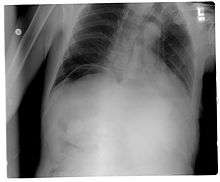

| Frontal chest X-ray. The air bubble below the right hemidiaphragm (on the left of the image) is a pneumoperitoneum. | |

Pneumoperitoneum is pneumatosis (abnormal presence of air or other gas) in the peritoneal cavity, a potential space within the abdominal cavity. When present, it can often be seen on radiography, but small amounts are often missed, and CT scan is nowadays regarded as a criterion standard in the assessment of a pneumoperitoneum.[1] CT can visualize quantities as small as 5 cm³ of air or gas. The most common cause is a perforated abdominal viscus, generally a perforated peptic ulcer, although any part of the bowel may perforate from a benign ulcer, tumor or abdominal trauma. A perforated appendix seldom causes a pneumoperitoneum.

Subphrenic abscess, bowel interposed between diaphragm and liver (Chilaiditi syndrome), and linear atelectasis at the base of the lungs can simulate free air under the diaphragm on a chest X-ray.